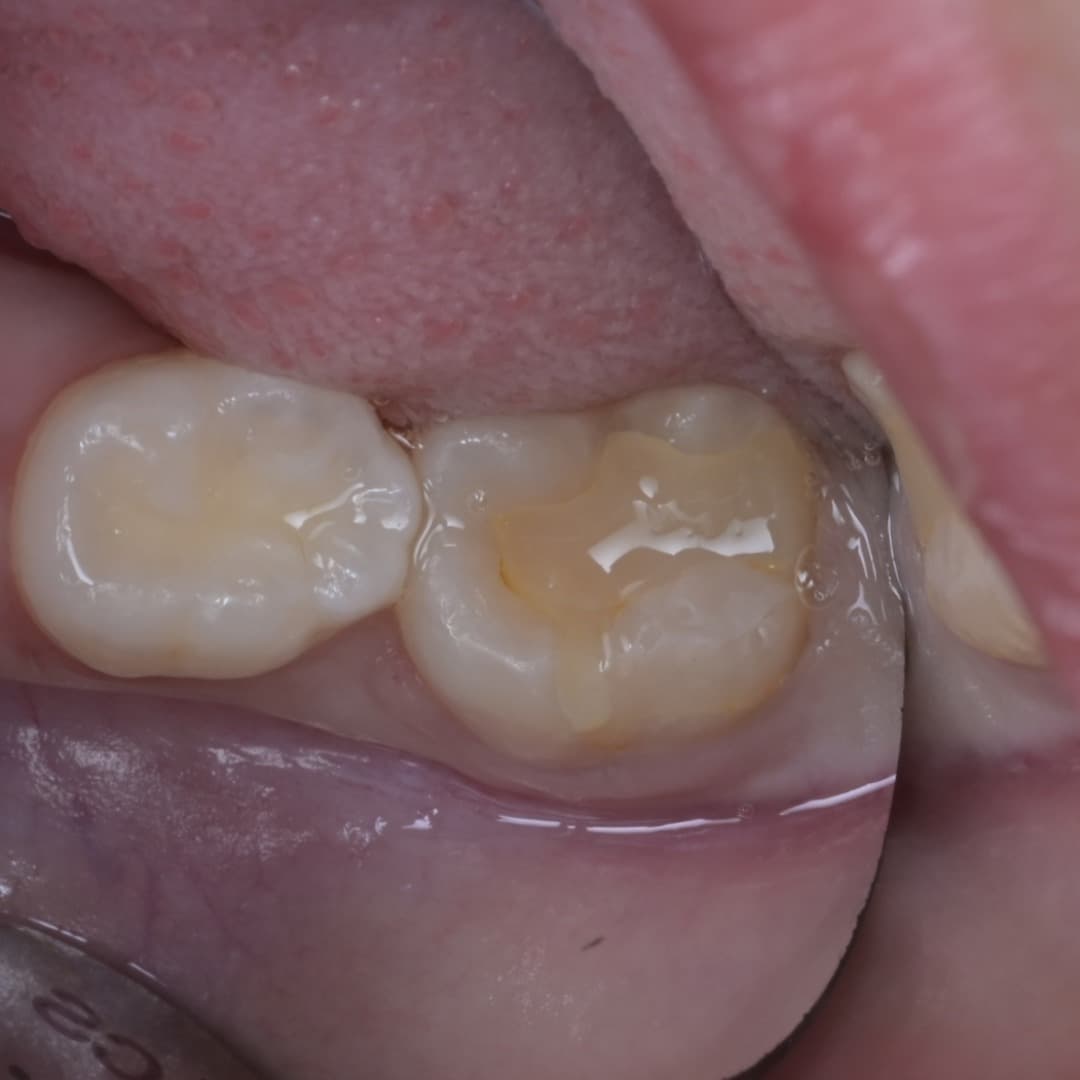

레진빌드업 · 2026.04.23

레진빌드업

2차우식이 생긴 인레이 수복물을 레진빌드업으로 재치료